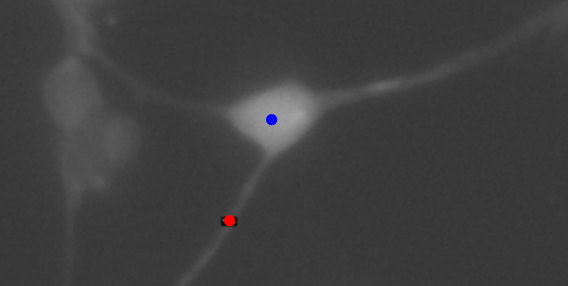

Figure 1. A sample cortical neuron with an axonal cut site (blue). The axonal strength was measured by the distance of the axonal gap (red).

RGCs from postnatal day-5 Sprague–Dawley rats were purified by immunopanning, separated, and cultured in a serum-free defined medium supplemented with BDNF, CNTF, insulin, and forskolin. To monitor intracellular calcium, all RGCs were loaded with the Fluo-4 indicator 40 min before ablation. Dishes were placed on a microscope in phase-contrast mode, and coordinates of RGCs meeting selection criteria (relative isolation, a clearly defined axon, and minimal surrounding debris) were identified and recorded.  The power before the objective was measured to be 250 mW.  The epifluorescence arc lamp was set to 2% to minimize fluorescence variation from light exposure. Fluorescence images were then collected every 10 s for 5 min to obtain baseline signals. The axon of an individual cell in each field of view was ablated with a 275 µW laser positioned 20 µm from the soma (as shown in Figure 3), and imaging was continued at the same rate for an additional 5 min post-ablation. Four RGCs served as non-ablated controls and were imaged for 10 min under identical conditions. After acquisition, fluorescence intensities at the ablation site and at the soma were extracted in ImageJ and normalized to each cell’s pre-ablation median fluorescence to account for differences in starting luminosity.

Figure 3. A sample RGC with the point of ablation highlighted in red. Fluorescence is measured at both the point of ablation (red) and the cell body (marked in blue).